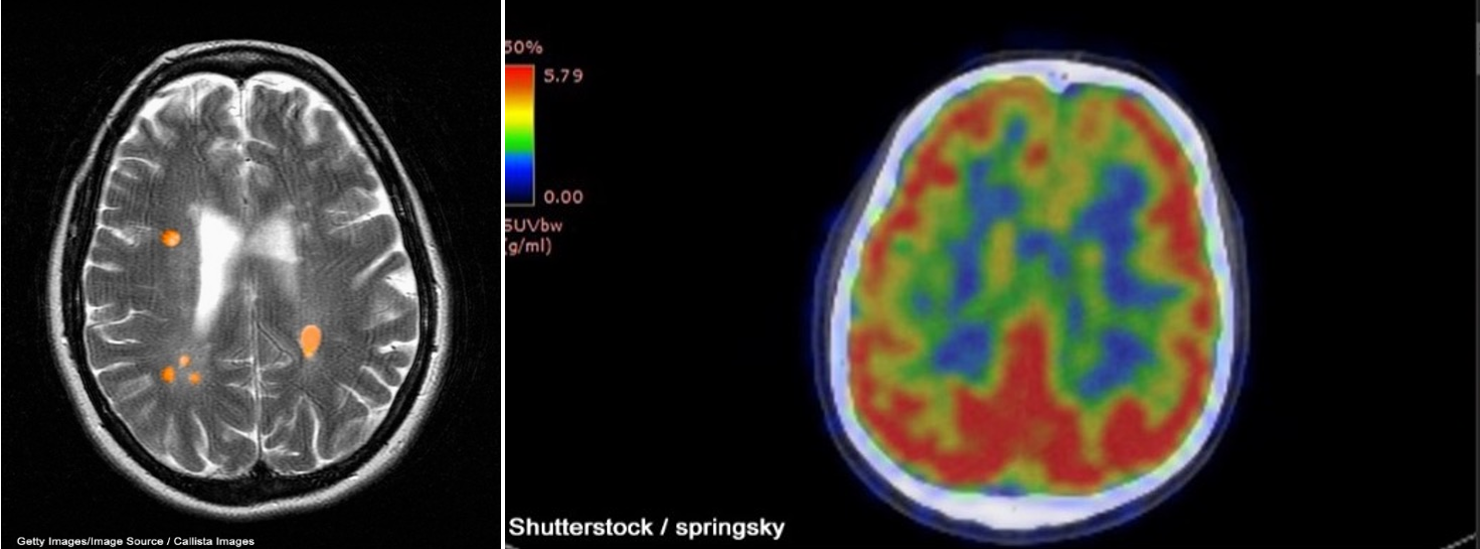

A CT scan can be used to obtain cross-sectional images of the brain to evaluate for structural abnormalities that may be causing the seizures, such as tumors, cysts, or bleeding. A CT scan is a 3-dimensional (3D) computer-generated graphic based on x-ray images. Similarly, an MRI can detect lesions or abnormalities in the brain using powerful magnets and radio waves. A more in-depth MRI called a functional MRI (fMRI) can measure the changes in blood flow within the brain, as seen in Figure 1a. An fMRI may be used before surgery to locate critical functions precisely, such as movement or speech, so the surgeon can avoid injury to those areas during surgery. PET scans can detect brain function abnormalities. A small amount of radioactive tracer material is typically injected to help visualize chemical activity in certain tissues, as seen in Figure 1b. If the MRI, EEG, or other tests could not determine exactly where the seizures originated, a single-photon emission CT (SPECT) scan might be conducted. This test uses a radioactive tracer to provide a detailed, 3D map of the blood flow through the brain during seizures (Adamolekun, 2022b; Haider & Bullinger, 2022).

Figure 1

fMRI (a) and PET (b) Brain Scan Images